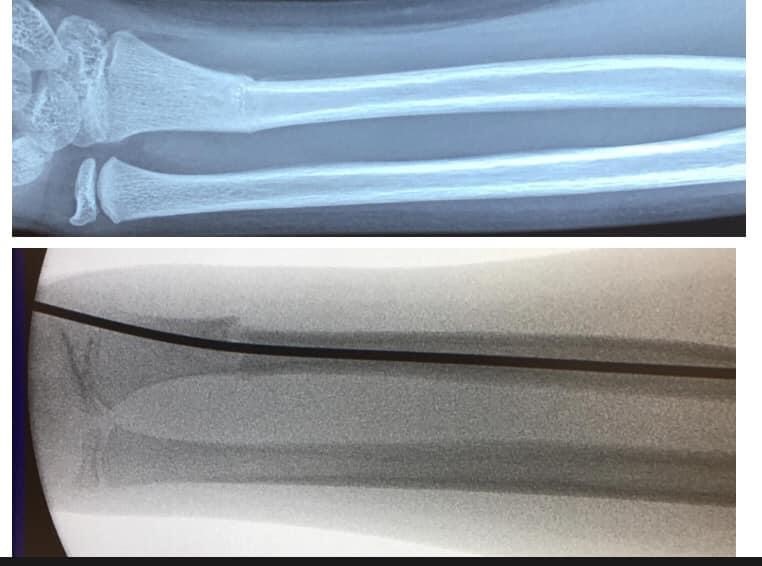

小童的骨質軟而有彈性,不用很大外力就能折彎,因此稍一不慎在耍樂蹦跳期間跌倒或從稍高位置跌下就有可能造成骨折。

常見會有外觀變形、彎曲的情況

醫生會先以X光去確定受傷位置和骨折的嚴重程度